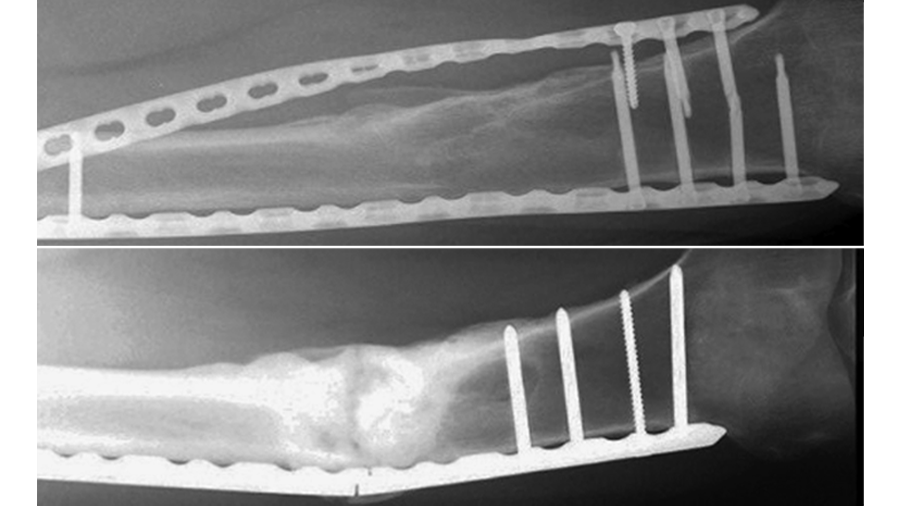

Two new hybrid locking pancarpal arthrodesis plates have recently been developed featuring a tapered profile and incorporating either a round (RH) or oval (OH) radiocarpal hole (Fig 1). The OH design was considered to facilitate both screw placement in the radiocarpal bone and plate positioning, but perhaps at the expense of mechanical strength. So far, neither mechanical comparisons between these plate designs have been performed nor the effect of an oval radiocarpal hole on the plate structural parameters investigated.

Plates with RH or OH design were prebent at 20° and assigned to three techniques for fixation of canine forelimb models with simulated radius, radiocarpal and third metacarpal bones. The OH plates were instrumented with the radiocarpal screw inserted either most proximally (OH-P) or most distally (OH-D) in the radiocarpal hole. Initially, all specimens were axially loaded to 300 N over 10 ramped cycles at 0.5 Hz (n = 6) and plate surface strains were measured with strain gauges placed at the areas of highest deformations as predicted by finite element analysis (Fig 2). The specimens were then subjected to cyclic axial loading at 8 Hz and 320 N peak load until failure to assess their fatigue life and mode of failure.